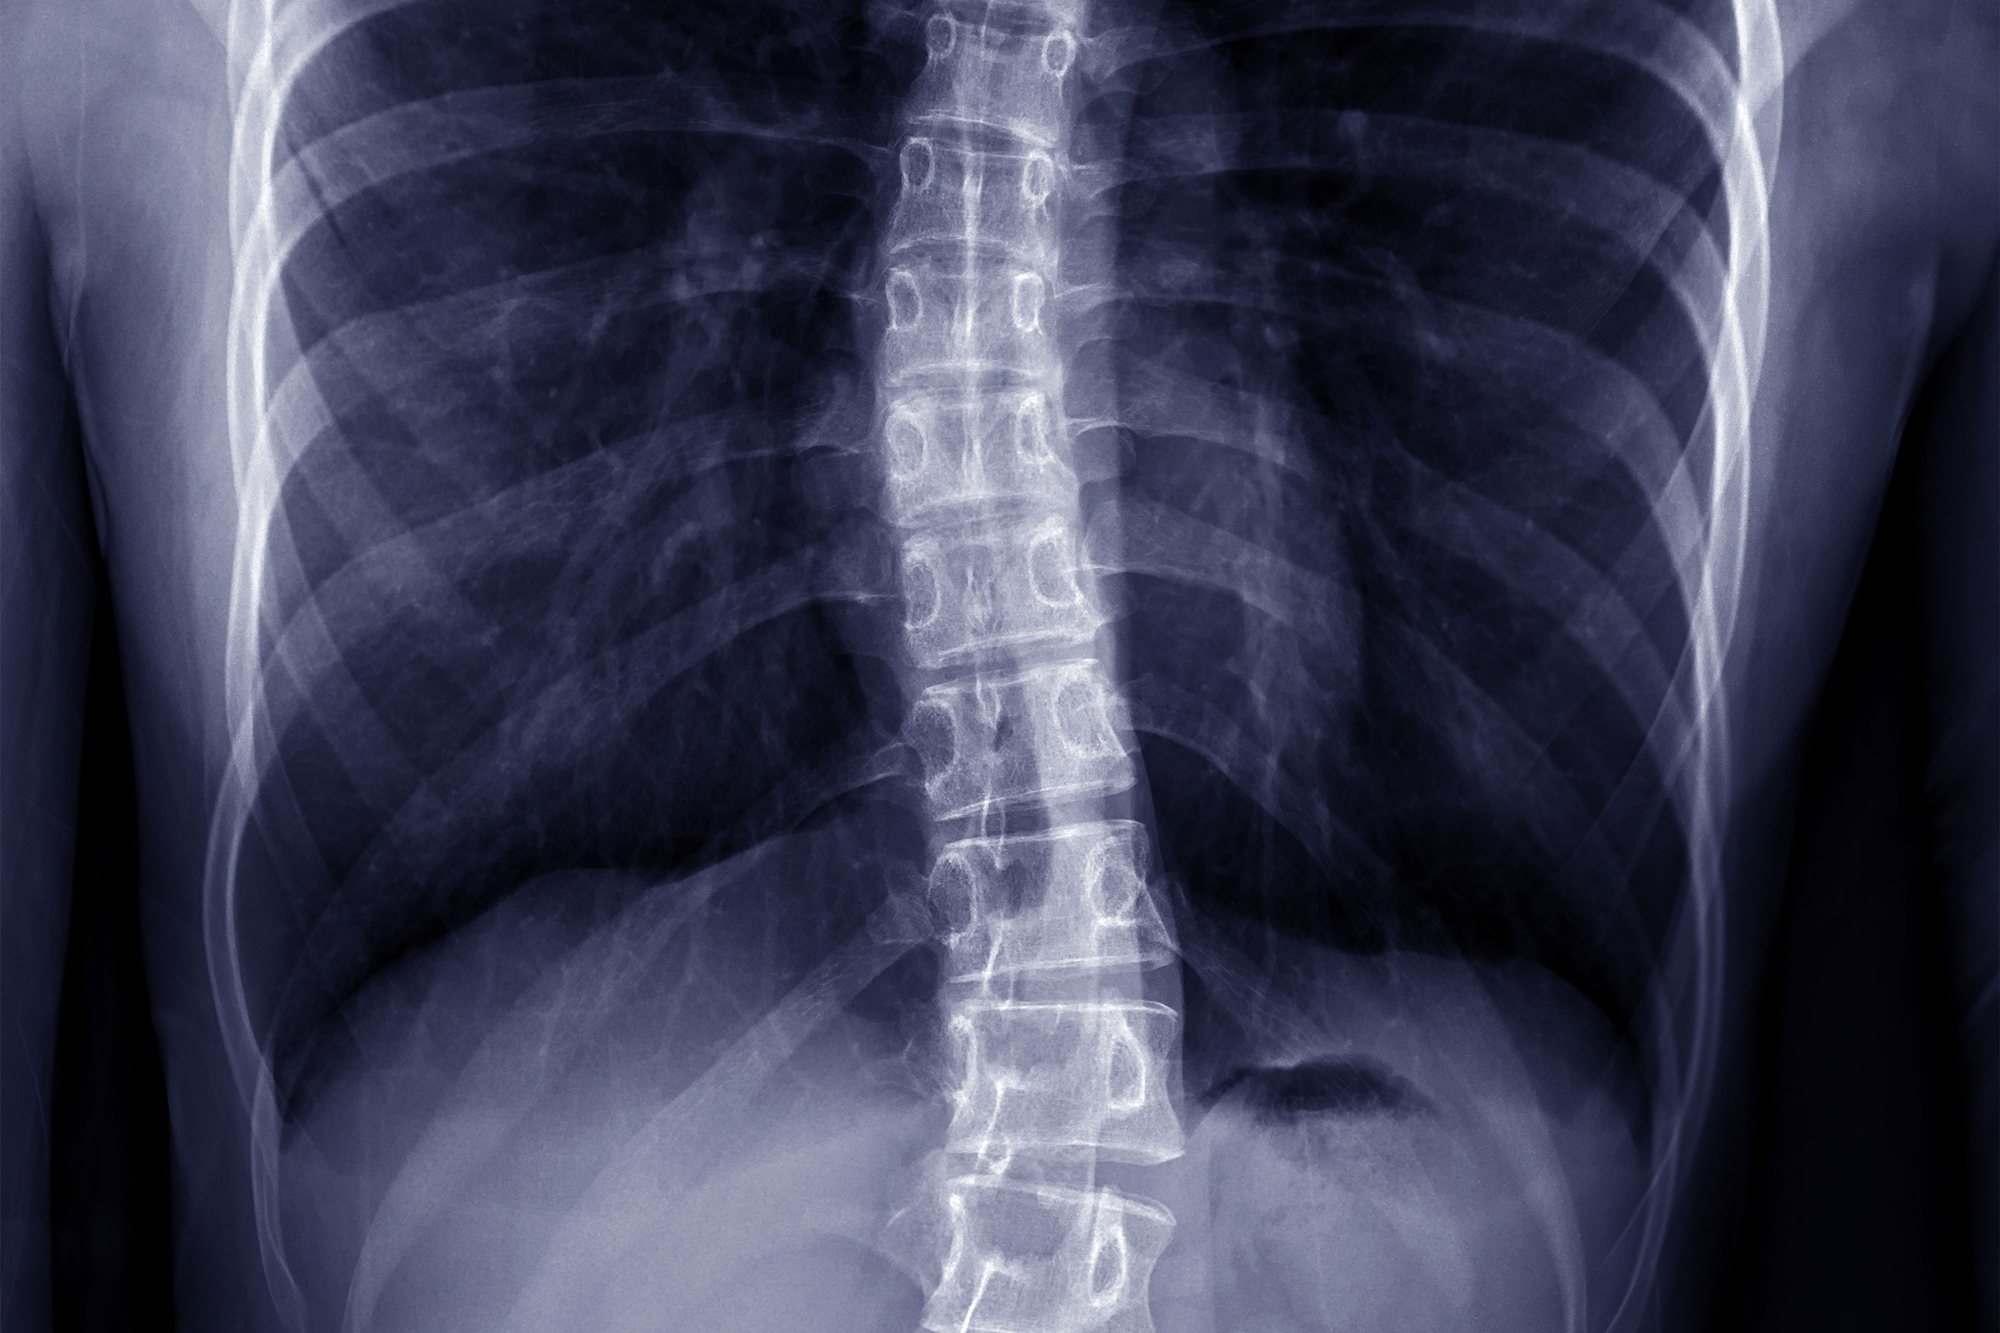

人體天生就是不對稱

根據解剖學的科學文獻及研究,發現人體右側橫膈膜較左側更大、更強壯,且右側附著點在脊椎上較低,這導致右側呼吸與姿勢主導優勢。器官位置(如肝臟偏右、心臟偏左)進一步強化這種不對稱,造成大多數人右腿負重偏好、右側旋轉傾向,並以右胸彎/左腰彎最常見(約佔90%)。

所以脊椎側彎是一件非常正常的事,是未經平衡的自然模式放大。因此,與其追求兩側完全對稱,集中減低兩側差異會是一個較為實際的做法。

所以脊椎側彎是一件非常正常的事,是未經平衡的自然模式放大。因此,與其追求兩側完全對稱,集中減低兩側差異會是一個較為實際的做法。